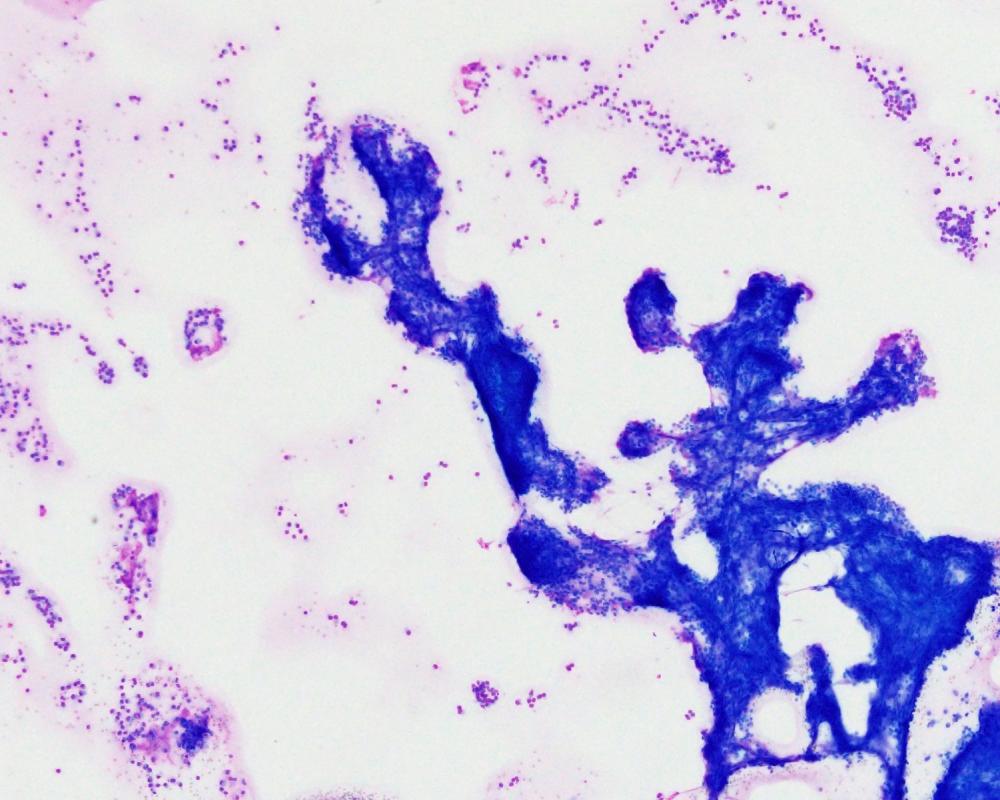

第40回日本臨床細胞学会九州連合会学会(大分)スライドカンファレンス症例3

種別:泌尿器

出題:橋向 圭介 熊本大学病院病理部

| 年齢 | 70代 | 性別 | 男性 |

| 採取部位 | 分腎尿 | 採取方法 | カテーテル |

| 検体処理法 | 2回遠心法(YM式液状検体固定液) |

既往歴:胸椎多発性骨髄腫治療中

現病歴:2021年より胸椎多発性骨髄腫の化学療法中であり、治験前スクリーニングの単純CT検査にて左尿管軟部影を指摘。同時期に腰痛、水腎症が出現し、精査目的のため分腎尿が提出された。

| 正解 | 5.形質細胞腫 |

▼選択肢及び投票結果

| 1.ウイルス感染細胞 | 21件 | (20.0%) | |

| 2.低異型度尿路上皮癌 | 8件 | (7.6%) | |

| 3.高異型度尿路上皮癌 | 30件 | (28.6%) | |

| 4.小細胞癌 | 3件 | (2.9%) | |

| 5.形質細胞腫 | 43件 | (41.0%) | |

| 投票総数 | 105件 | (100%) |